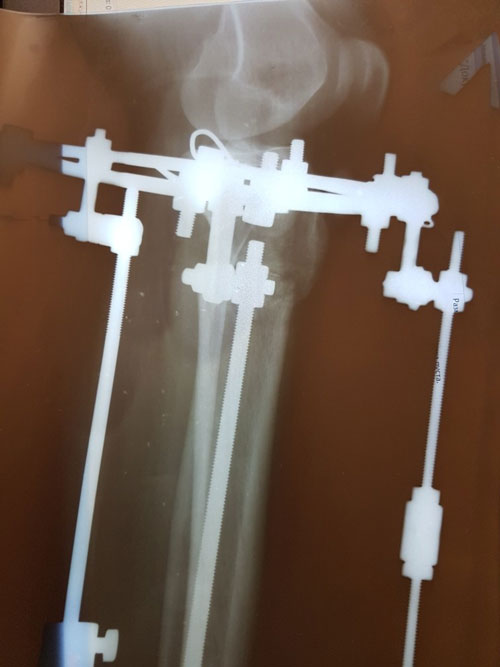

Дата операции 15.03.2017г.

Дата снятия аппаратов 23.06.2017г.

Срок лечения 97 дней.